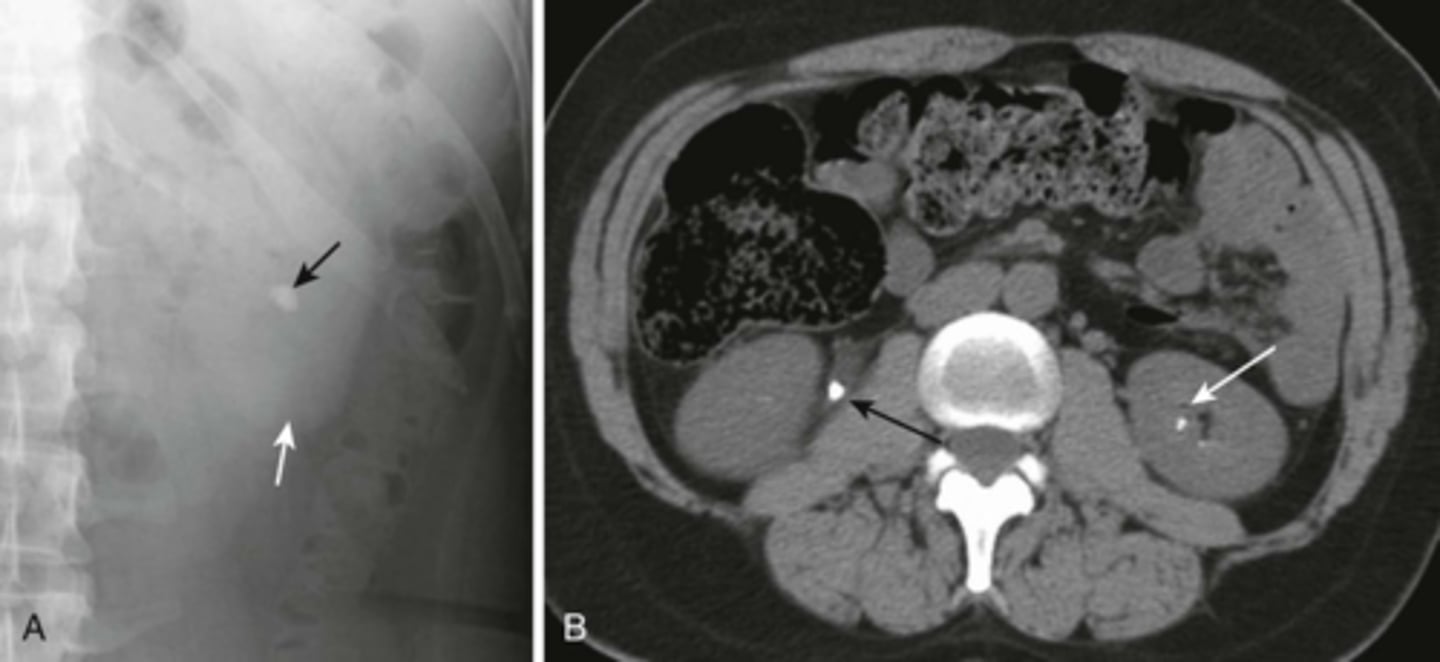

Renal calculi

BLACK ARROW: calcification

WHITE ARROW: shadow of left kidney

B:

BLACK ARROW: large calcification in the proximal right ureter

WHITE ARROW: smaller calcification in the left intrarenal collecting system.

Medullary nephrocalcinosis.

WHITE ARROWS: cloudlike calcifications seen bilaterally.

suggests that these calcifications have formed within a solid organ or tumor.

The calcifications conform to the distribution of the renal collecting systems.

This is medullary nephrocalcinosis, a condition not synonymous with renal calculi because nephrocalcinosis signifies a metabolic derangement. This patient had primary hyperparathyroidism.